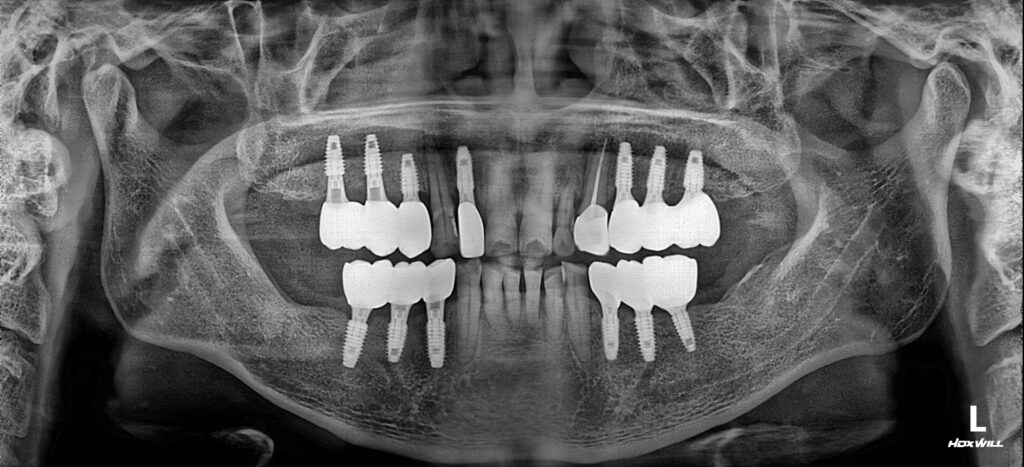

모든 치료가 마무리된 모습입니다!

워낙 치조골의 상태가 좋지 않으셔서 난이도가 높은 임플란트 식립이었으나 서울화이트S치과의 풍부한 수술경험과 3D CT 및 정밀한 장비로 해부학적 특징을 정확하게 분석하고 진행하여 성공적으로 마무리할 수 있었습니다.

환자분께서도 너무 좋지않은 상태였기때문에 큰 기대를 하지 못하셨는데 너무 달라진 일상생활을 할 수 있게되어서 서울화이트S치과에 고맙다고 말씀주셨어요:)